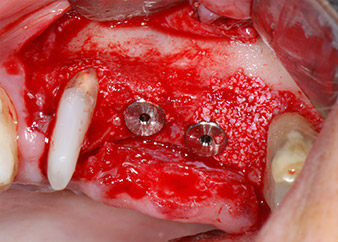

След един месец, в деня на операцията, болката и възпалението в зъб 24 е минимално, но подвижността в Miller class 2 е на лице. След отваряне на ламбата и почистването на периапикалната и перирадикуларната тъкани, обхватът на костния дефект стана очевиден (Фиг. 2 и 3).

В букалния корен, цялата вестибуларна и дистална кост липсва. Захващането е значително ограничено до палатиналния корен, подчертавайки предварително лошата прогноза. Зъб 27 също откри намалено хоризонтално захващане и минимално апикално разреждане (Фиг. 1) без клинични симптоми.

Въпреки това, ние се придържахме към първоначалния си план да запазим и двата зъба като абатмънти за временен мост по време на 6-месечната остеоинтеграция на имплантите. При повторна интервенция, ситуацията трябва да се преразгледа. Първо, в опит да се овладее ендо-перио проблема, останалата повърхност на зъба е внимателно обработена с пиезохирургично оборудване (Piezomed, W&H, използван с накрайник S1 под формата на шпатула, първоначално проектиран за ерозия на латералната синусна стена) (Фиг. 4).